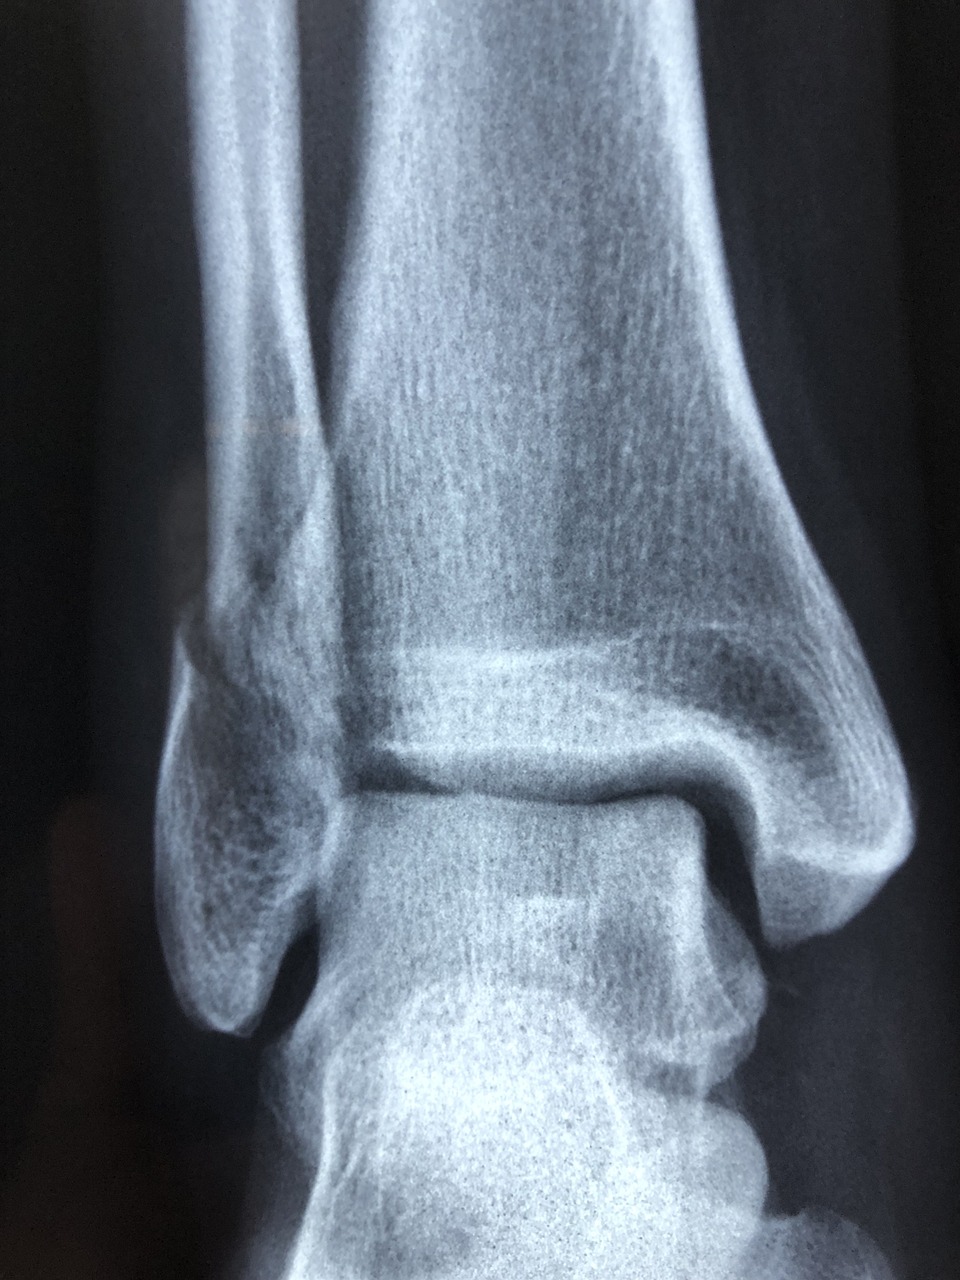

5. 검사 방법 (DXA·QUS)

| DXA (이중에너지 X선 흡수계측법) | 요추·대퇴골 촬영 | 정확도 최고, 국제 표준 | 방사선 노출, 비용↑ |

| QUS (정량적 초음파) | 발뒤꿈치 초음파 | 간단·저렴, 방사선 無 | 정밀도 낮음 |